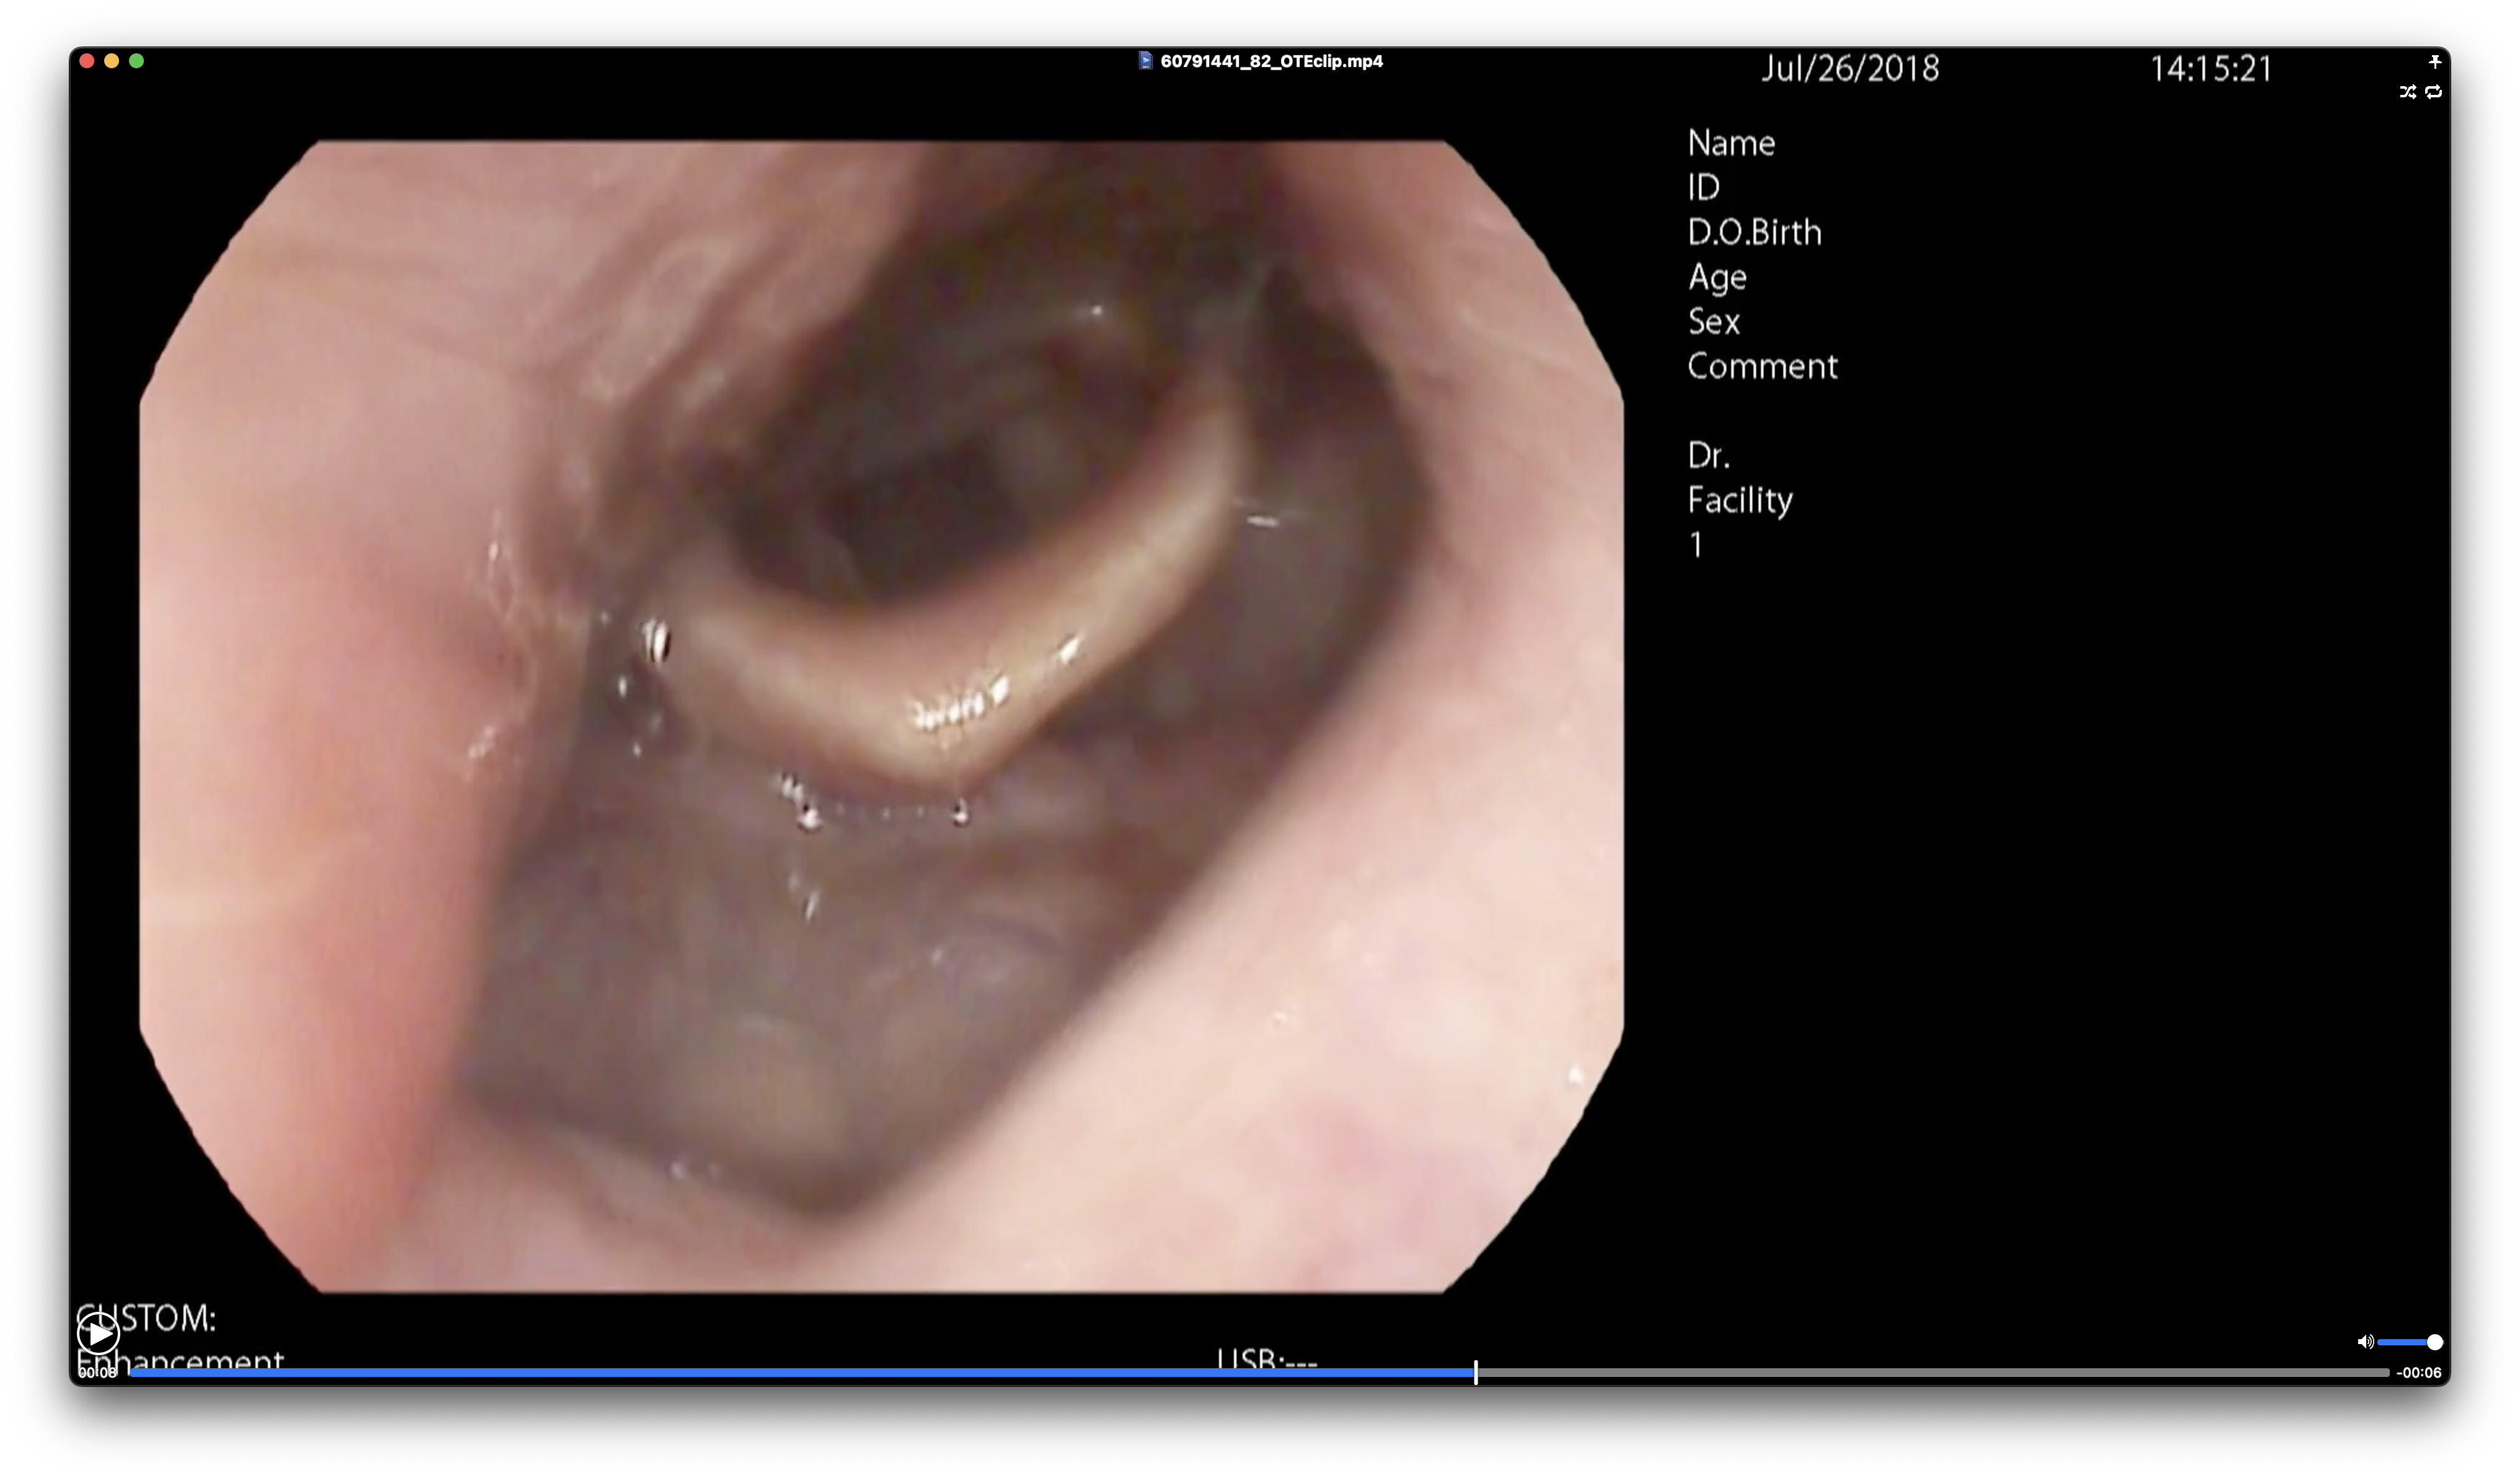

- 수면무호흡증이 발생하는 폐쇄 부위와 폐쇄 정도 분석을 위한 약물유도 수면내시경 환자 영상을 사용하여 구축된 폐쇄부위별 클립동영상 데이터와 이미지 데이터

약물유도 수면내시경 영상에서 폐쇄가 발생하는 Velum 영역과 OTE 영역에서 2호흡 길이를 가지는 클립동영상(mp4)와 이에 대한 영상 정보와 임상정보로 작성된 라벨링데이터(json)로 구성

약물유도 수면내시경 영상에서 폐쇄가 발생하는 Velum 영역과 OTE 영역에서 추출한 이미지(png)와 이에 대한 영상 정보와 임상정보, 세그멘테이션 정보로 작성된 라벨링데이터(json)로 구성